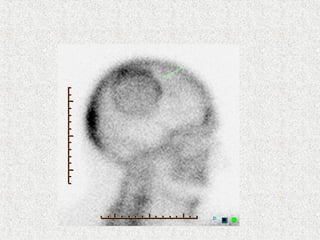

 Skull

 Circumscribed patch of osteoporosis in skull

 Osteoporosis circumscripta

 Cotton wool appearance

 Mixed

 Diploic widening

 Tam o'Shanter sign

 frontal bone enlargement, with the appearance of the

skull falling over the facial bones, like a Tam o'

Shanter hat